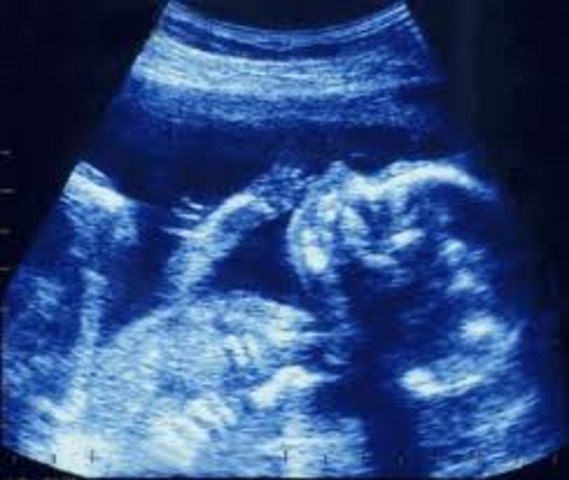

Encuentro con la ecografía

Antes de nacer los medicos hacen pruebas a mi madre para diagnosticar posibles problemas en el feto, esto es gracias a la ecografía que ya existe en nuestro mundo. Información de ecografía